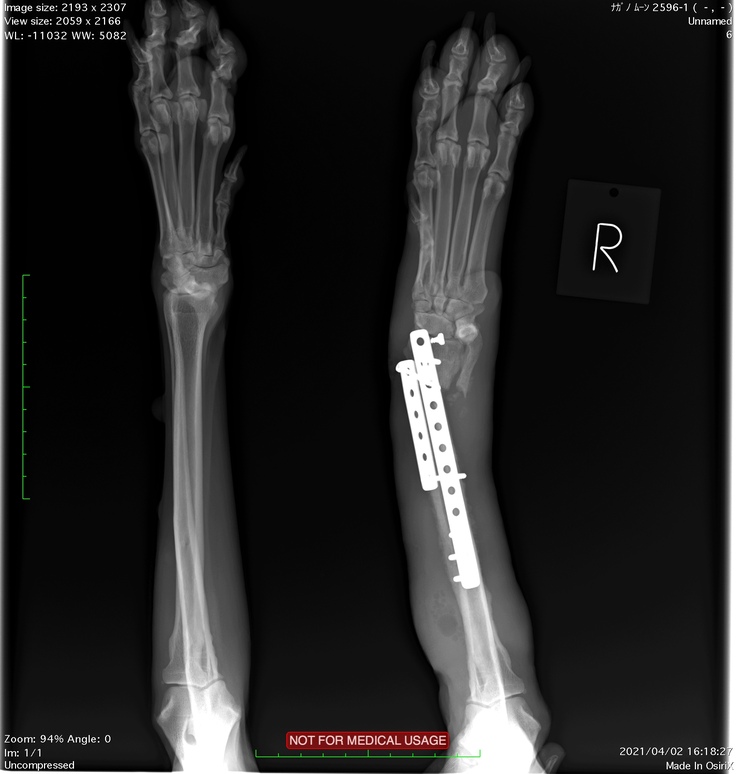

大津動物クリニックではクラウドファンディングのお話をしたらレントゲンの画像もご提供いただけました。

2度目の手術前のレントゲンです。

足先側のビス(釘)が折れて足が曲がってしまっています。

2度目の手術後のレントゲンです。まっすぐになりました。